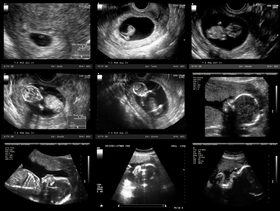

بعد الإجهاض في الشهر الثاني من الحمل، من الطبيعي أن تخضعين للكشف الطبي وللفحص بالموجات فوق الصوتية للتأكد من وجود بقايا الحمل في الجسم. وفي حال وجود هذه البقايا، ستخضعين الى عملية تنظيف الرحم التي تتم من خلال إجراء عملية شفط لجدار الرحم وتنظيفه وهي تستغرق لحوالي 15 دقيقة فقط.